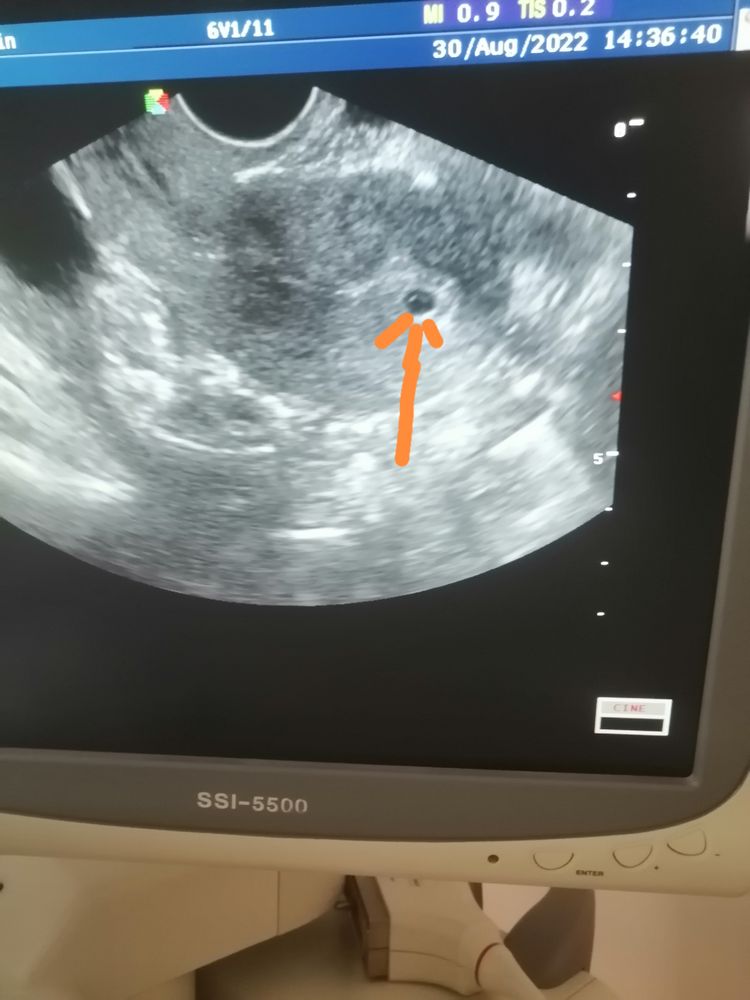

20дпп,сходила я сегодня на узи... Плодное яйцо 4,5мм..Срок по акушерским данным 4 недели 4дня...плодное яйцо в матке 🥰🙏...

PS:a внутри что-то виднеется, что это может быть 🤷♀️ 🤔